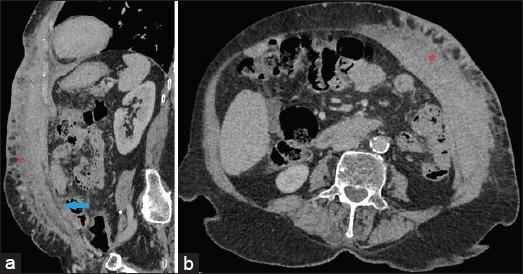

A total of eight cases were identified, out of which seven were females. The most common presentation consisted of the presence of metastatic nodules which were seen in 62.5% (five out of eight) of the patients. Other features consisted of erythematous or plaque-like skin thickening on clinical examination, increased density with indistinct margins seen on a mammogram and diffuse oedematous changes in the skin with small irregular mass or infiltration into subcutaneous tissues were visualised on ultrasound and CT studies.

Skin metastasis from breast cancer most commonly presents as nodules, although rarely they may present as plaques or diffuse skin thickening. Awareness of diverse manifestations of skin metastasis is of utmost importance in early diagnosis and management.